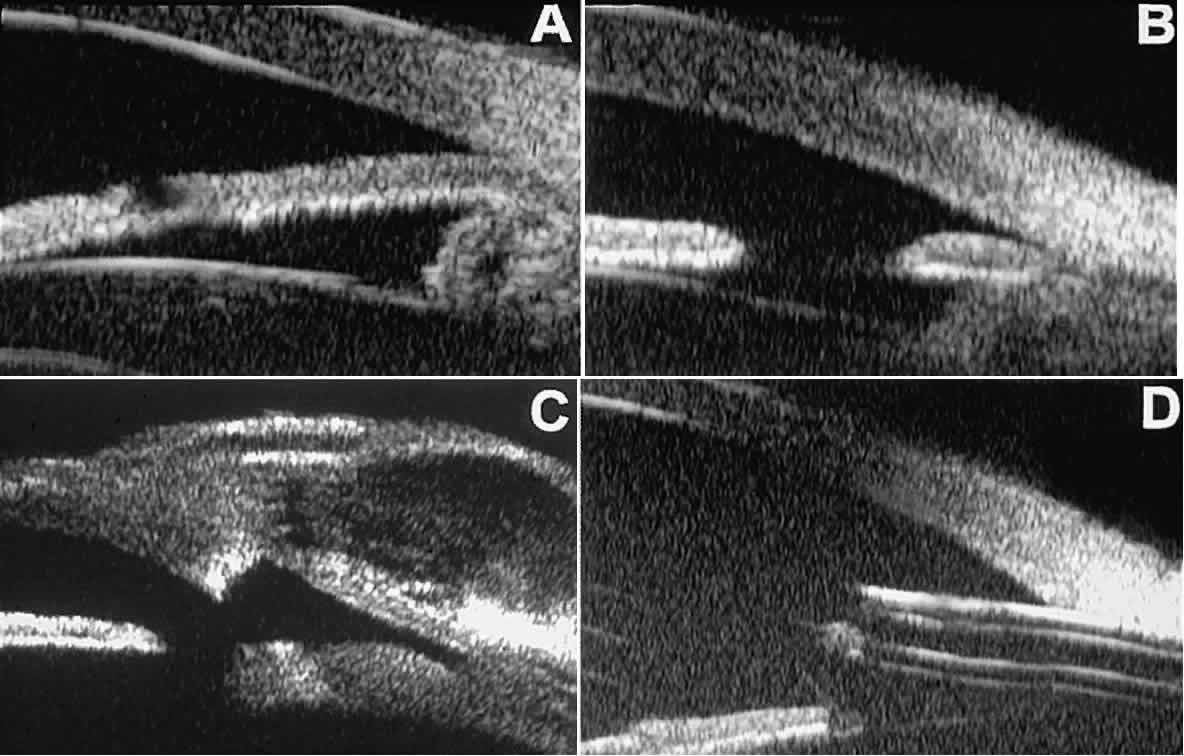

In eyes with a narrow angle, UBM shows the extent of angle closure, reveals the depth of the anterior and posterior chambers, and identifies pathologic processes pushing the lens and iris forward (Fig. 11).2–4,8 UBM has been able to differentiate between primary angle closure (i.e., cases of angle closure without additional pathology responsible for the anterior lens-iris displacement [see Fig. 11A] and secondary angle closure due to processes such as lens swelling and dislocation (see Fig. 11B), massive hemorrhagic retinal detachment pushing the lens and iris anteriorly (see Fig. 11C), and multiple neuroepithelial cysts of the iridociliary sulcus (see Fig. 11D).

Fig. 11. Angle configuration in eyes with angle-closure glaucoma. A. Primary angle-closure glaucoma with anterior displacement of lens and iris. B. Angle closure secondary to swollen, cataractous lens (phakomorphic angle closure). C. Angle closure secondary to massive hemorrhagic retinal detachment; the subretinal blood is evident in the lower right corner of the photograph. D. Angle closure secondary to multiple peripheral iris cysts.